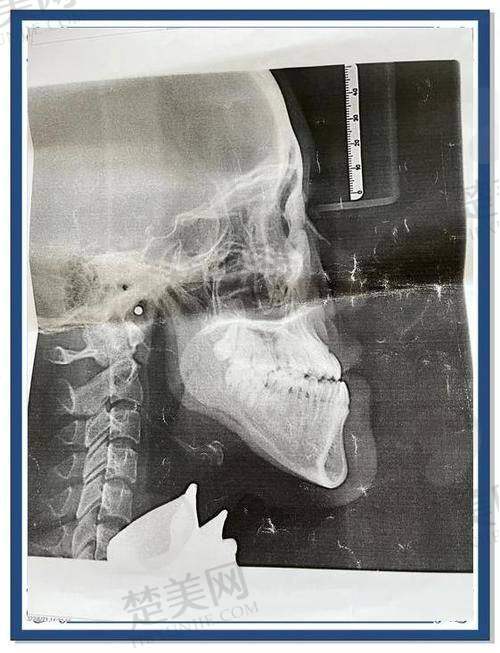

1. 骨性地包天矫正实例:有一位患者因骨性地包天接受手术,术前没有进行正畸治疗。艾伟健医生采用了 SSRO 下颌支矢状骨劈开术,通过打断下颌支并向后回缩来调整咬合关系。术后右侧截骨量在 7.3 - 7.6mm,左侧在 3.4 - 4.0mm,成功实现了上下颌骨的重新对齐。这位患者表示,艾医生手法稳,术中出血量少,术后肿胀较轻,大概三个月左右就修复得比较自然了。而且地包天正颌矫正的价格相对来说也比较合理,36000 元起。